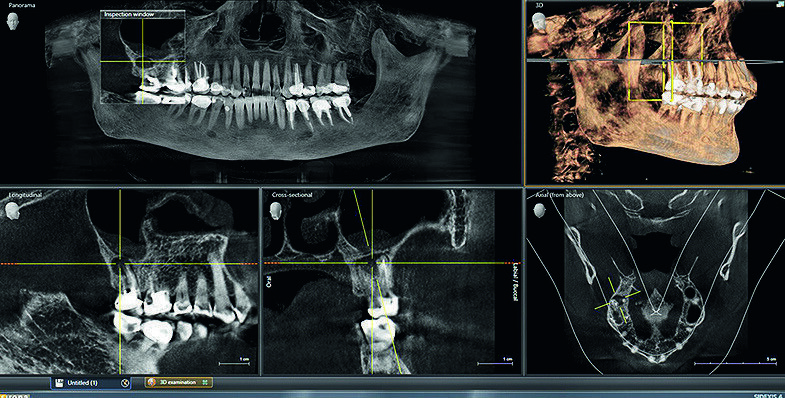

3D examination in Sidexis 4.

For the treatment plan, we utilized 3D imaging data to create an OPTISLEEP oral appliance. The fully digital workflow is efficient and the appliance can be ordered directly through the SICAT Air software, with the end result being a very happy patient. This was a particularly rewarding case because, after wearing the appliance, the patient remarked that she had not had a restful night’s sleep for so long that she had forgotten what it was like to wake up feeling rested.